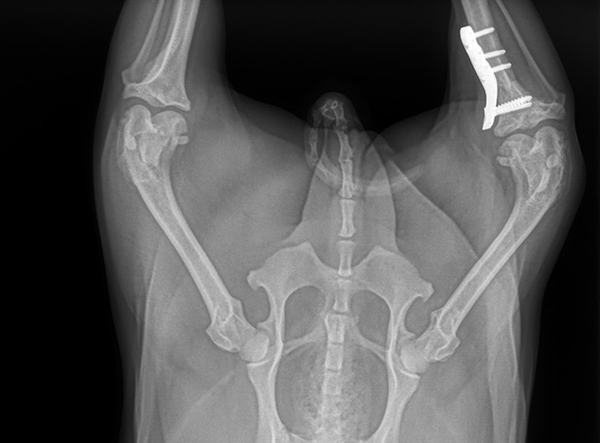

Today’s patient was a petite, 5 kg mixed-breed dog with a cruciate ligament injury. To address the biomechanical demands and ensure long-term stability, a 2.0 mm LeiLOX TPLO Plate was used. The miniaturized plate design allowed for precise anatomical fit without compromising strength.

The surgery was completed smoothly, and postoperative radiographs confirmed excellent alignment and fixation. With controlled rehabilitation, the patient is expected to regain full mobility and enjoy a pain-free return to daily activity.

Implant Used: 2.0 mm LeiLOX TPLO Plate Stainless Steel Plate (also available in Titanium)